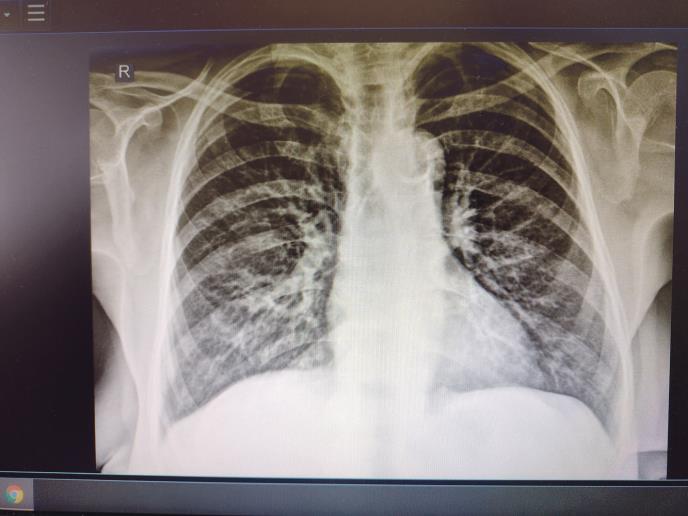

Kod dr Alekse Živkovića od ranog jutra se smenjuju. S rendgena upravo došao Miloš Stanković od 32 leta - početna upala pluća.

- Iako mu je saturacija bila sjajna - 99, na slušalicama sam čuo da ima upalu. I to nije neretko - priča dr Živković dok određuje terapiju - antibiotik, probiotik, kortikosteroidi...

Stiže i deka od 83 godine. Doveo ga zet od unuke. Vakcinisan jeste, ali i godina i bolesti. Upala pluća, saturacija 94. Mora dalje, kandidat za bolnicu.

- Prvi pacijent danas koji mora na trijažu za bolnicu. Već ima tzv. mlečno staklo na plućima. Nema puno slanja u bolnice kao ranije, još ima upala pluća i delte, ali sada ih je više blažih i srednjih, lečenje je kući uz antibiotike i koritkosteroide. A i retko se pacijenti kasno jave - priča dr Živković.